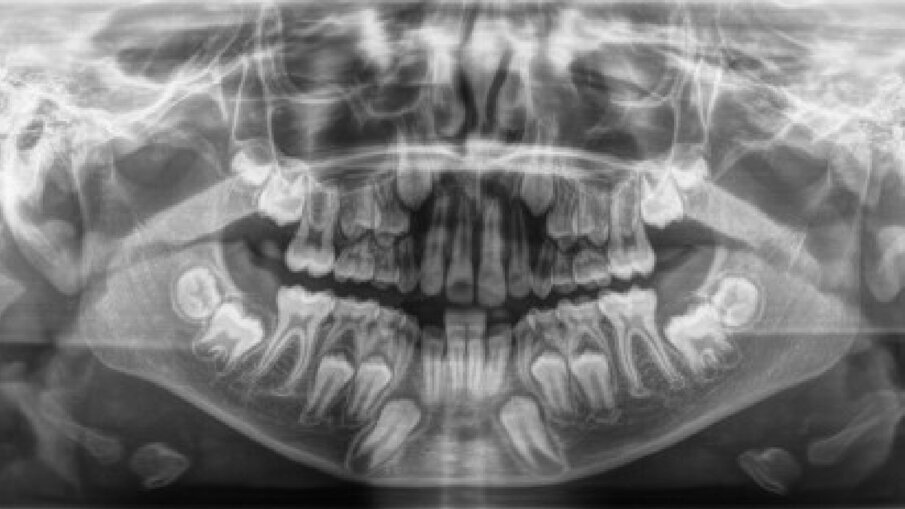

Il paziente, maschio, di 10 anni e mezzo, in dentizione mista. Le arcate dentarie sono in prima classe molare e canina. È presente un overjet di 1 mm e le linee mediane sono centrate. Si osserva un leggero affollamento in entrambe le arcate. Viene raccolta tutta la documentazione clinica per la valutazione del caso ed il successivo trattamento. Si procede alla presa delle impronte per i modelli da studio (Fig. 2). Vengono effettuate l’RX OPT (Fig. 3), la teleradiografia latero-laterale del cranio (Fig. 4) e l’analisi cefalometrica (Fig. 5, Tab. 1). Dopo un anno di terapia intercettiva, è stato eseguito un controllo con una rx OPT per valutare lo stato della permuta dentaria (Fig. 6). All’RX OPT si osserva l’inclusione intraossea con mesio versione dell’elemento 4.3. La CBCT è stata eseguita per valutare la posizione dell’CMI rispetto alle strutture anatomiche vicine (Fig. 7). Il CMI è stato valutato secondo la classificazione di Mupparapu5 nel tipo numero 1. Nella CBCT si osserva parte della corona del 4.3 a contatto con gli apici delle radici degli incisivi inferiori (4.1 e 4.2).

Fig. 6_RX OPT con inclusione dell’elemento 4.3.